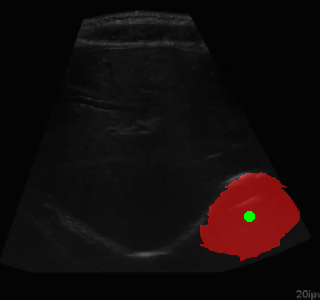

This project combines deep learning-based image segmentation with reinforcement learning to automatically navigate to regions of interest in ultrasound images. The system consists of three main components:

The trained agent successfully navigates to the centers of the segmented regions with a high success rate. The improvements to address oscillations significantly enhanced the agent's performance.